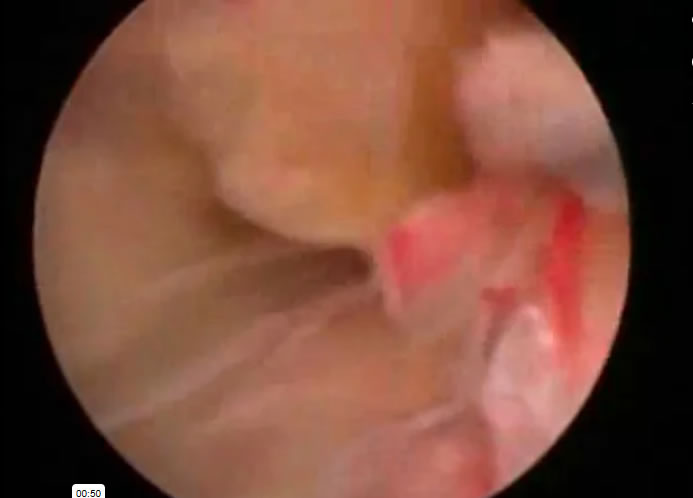

Medicos Cirujanos > Coloproctologos

Medicos Cirujanos > Endoscopistas